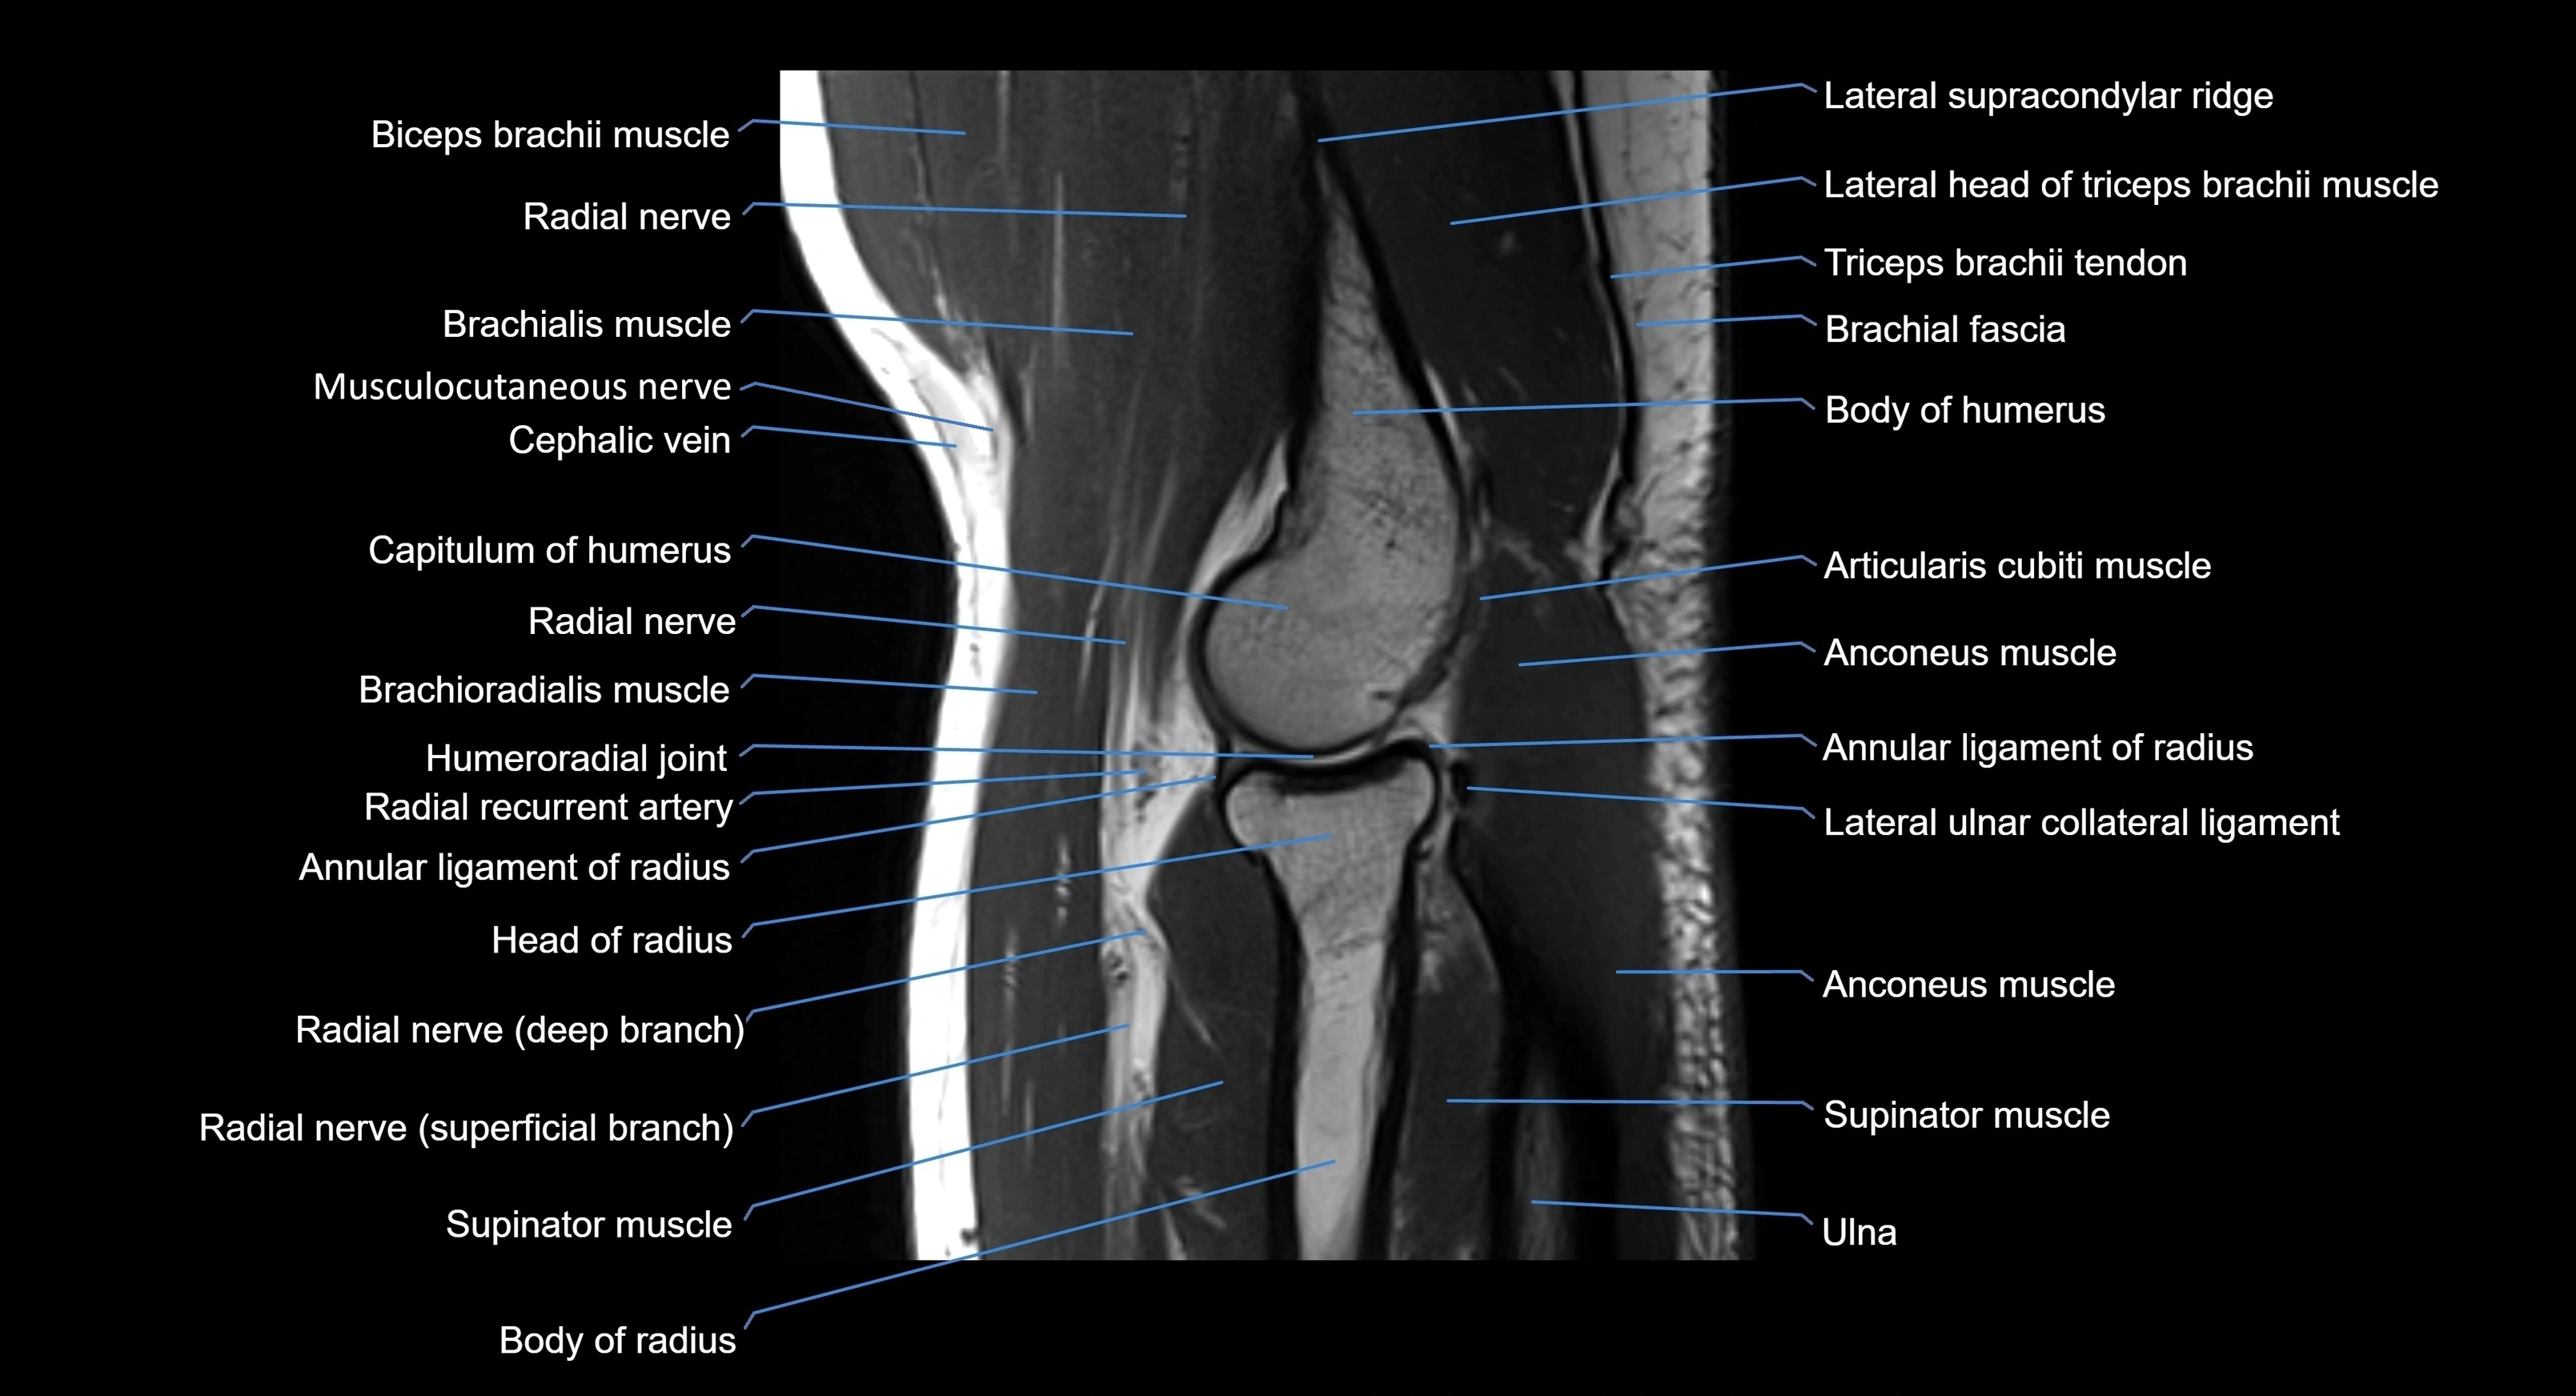

MRI image

image